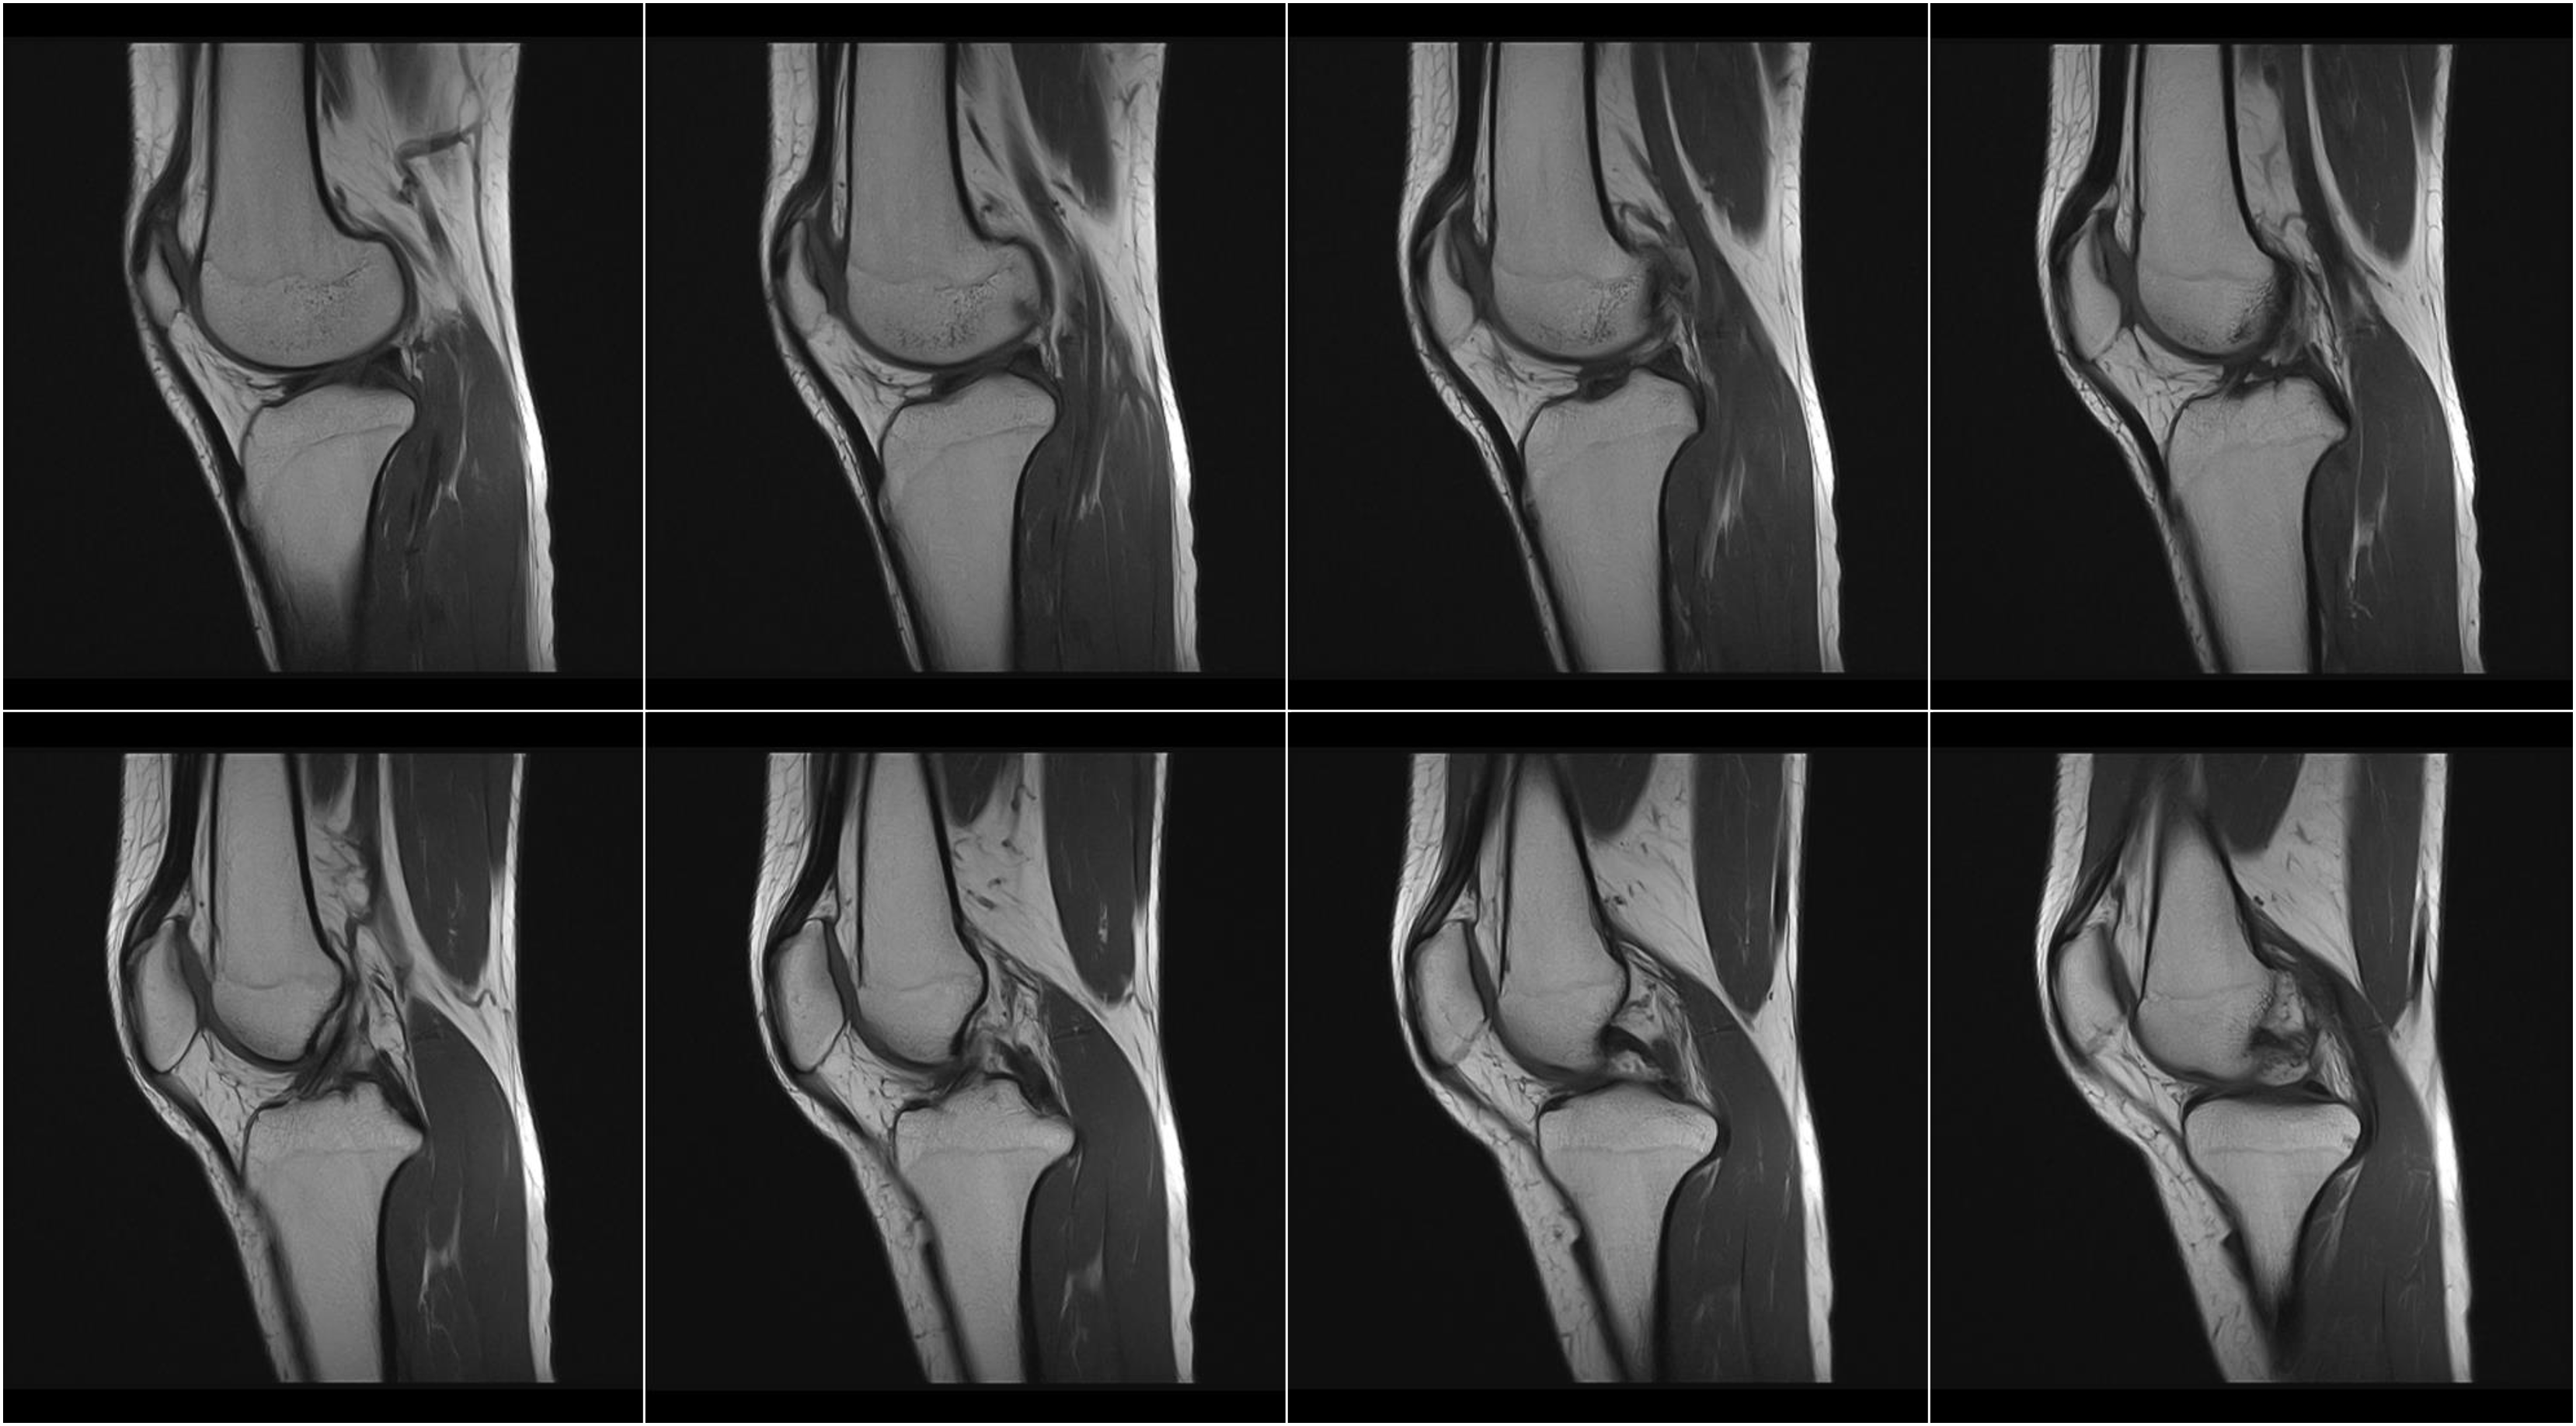

Hình ảnh lâm sàng